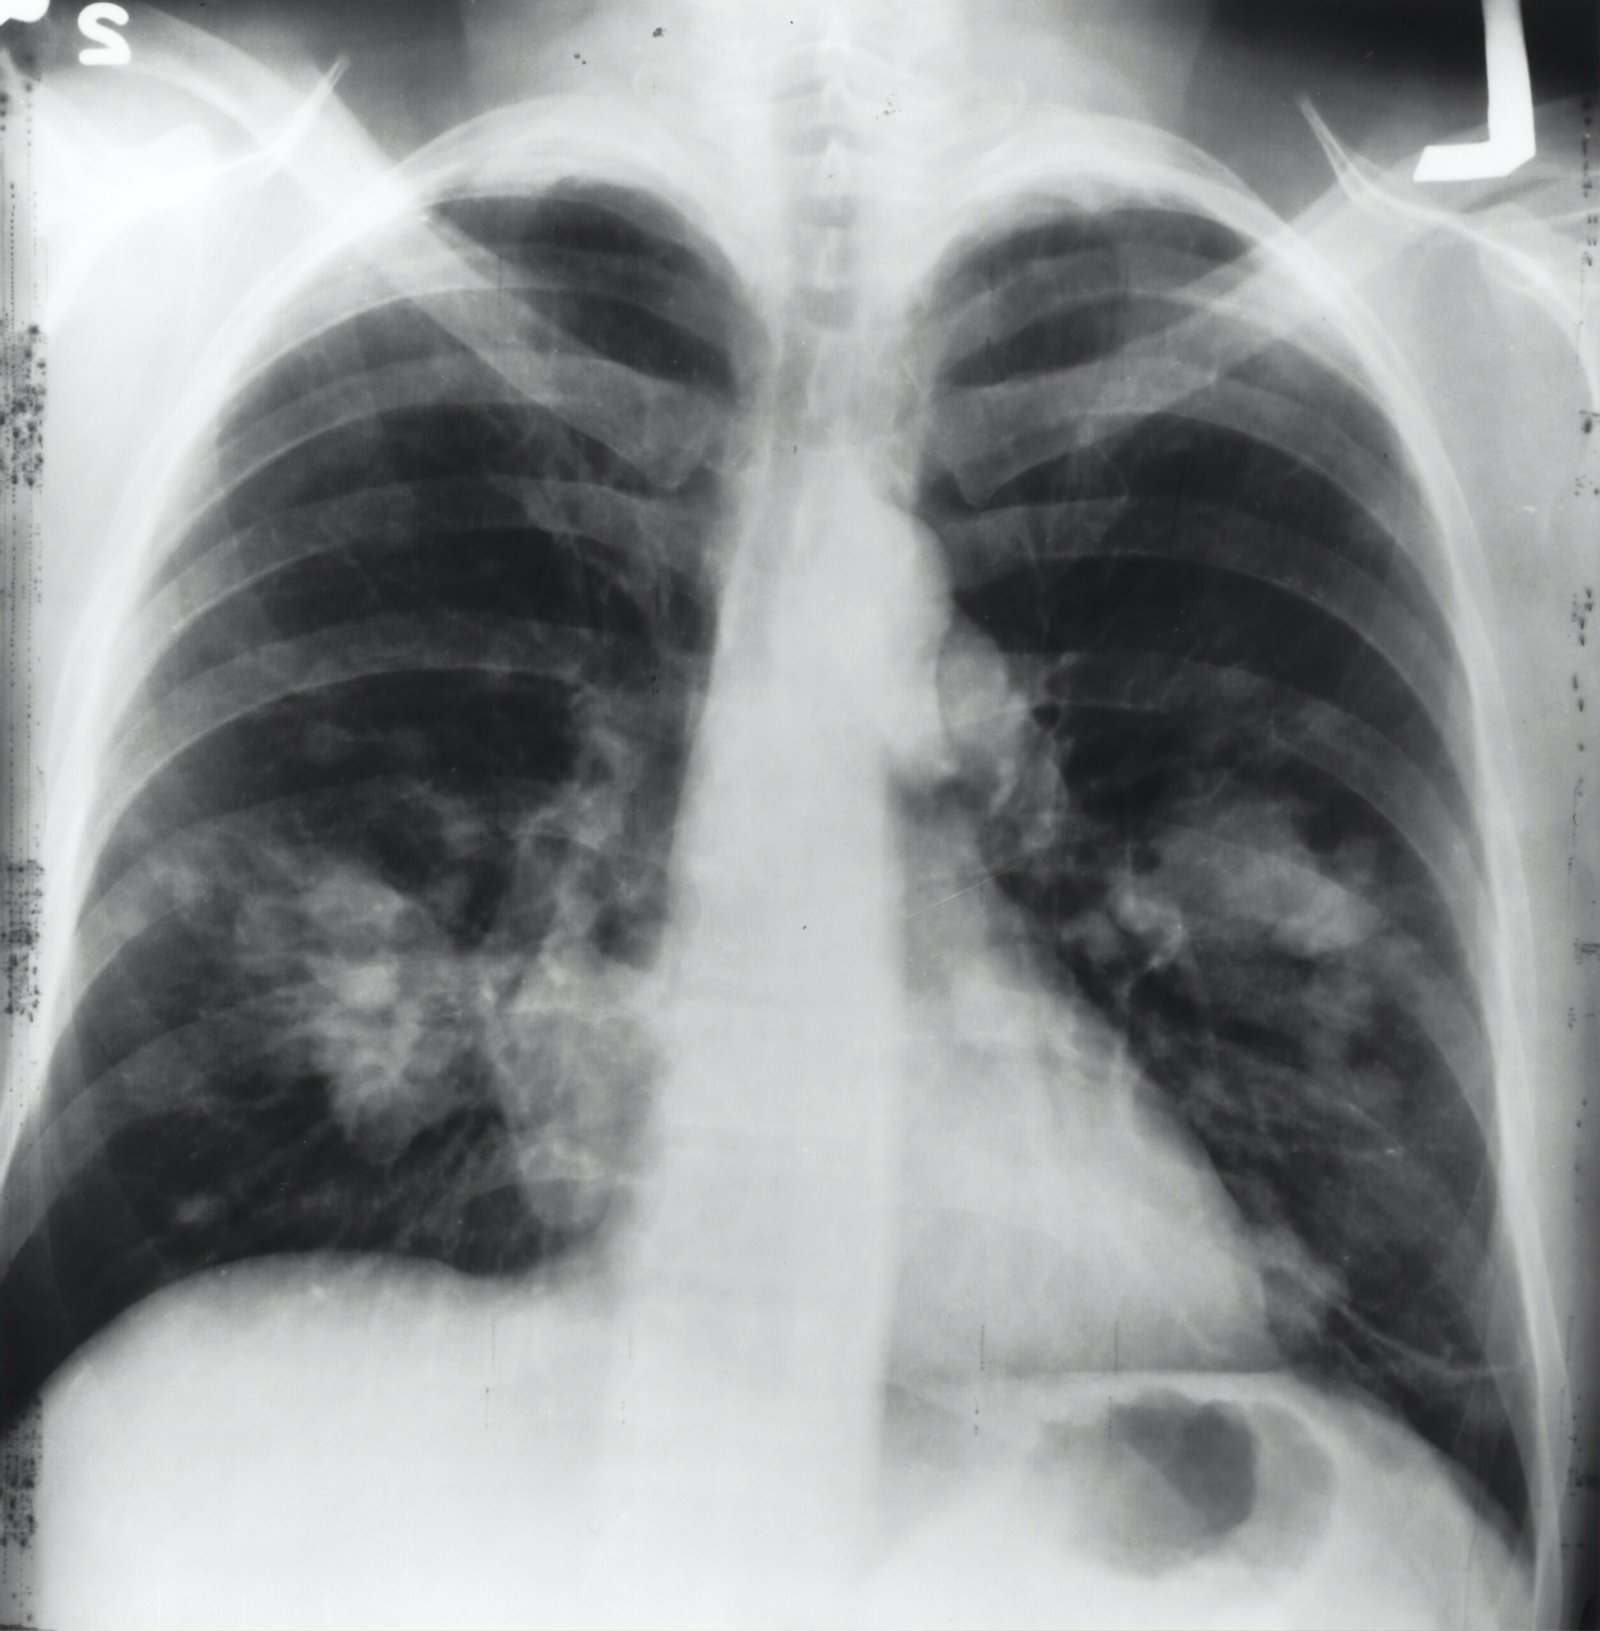

enfisema polmonare

Enfisema

Enfisema Forse non è impossibile non solo gestire la malattia, prevenirne l’aggravamento ed aumentare l’ossigenazione dell’organismo, ma[…]